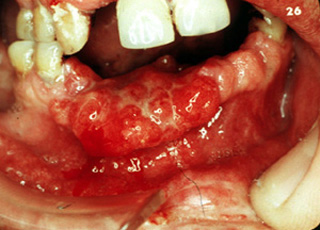

Cáncer grande

El crecimiento continuado de un carcinoma pequeño puede producir una lesión de esta naturaleza que involucra

gran parte del piso de la boca. Es una situación sumamente seria en esta fase, aunque el cáncer no es particularmente grande. Hay

una gran posibilidad de metástasis de los ganglios, que desgraciadamente, es a menudo bilateral cuando los tumores están en

la linea media. La terapia, incluso para este cáncer relativamente pequeño, debe ser

extensa y debilita al paciente.